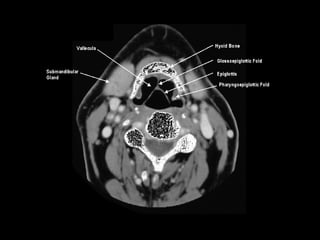

Radiographers use medical imaging equipment like X-rays and MRIs to produce images of patients' internal structures and organs. They are responsible for positioning patients, operating scanning machines, and ensuring quality images. Radiographers must have strong attention to detail, excellent communication skills, and the ability to work well under pressure to accurately capture anatomical features and diagnose any abnormalities.